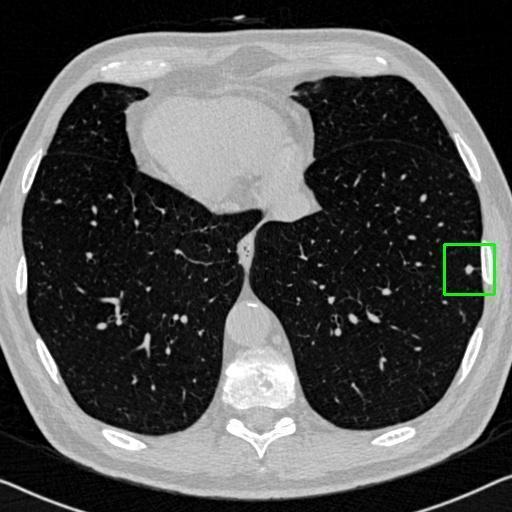

We developed an AI-based system using deep learning models for analyzing lung CT scans to detect and classify pulmonary nodules. We chose the YOLOv11 architecture for its enhanced object detection capability and adapted it specifically for medical imaging, incorporating pixel-level precision and severity classification.

Classification into three severity levels with colored bounding boxes.

Designed a severity classification system that categorizes nodules into null, moderate, and severe using colored bounding boxes, assisting in rapid clinical decision-making.